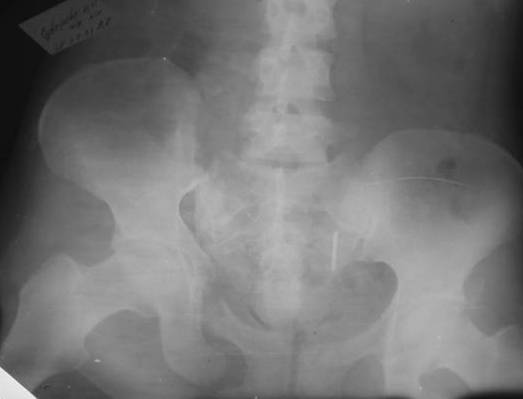

Пациентка С.26 лет. Травма за 6 месяцев до поступления

Укорочение правой нижней конечности до 10см

23.09.2003. Одновременный остеосинтез переднего и заднего тазовых полуколец

Результат через 10 дней  и  8месяцев после операции